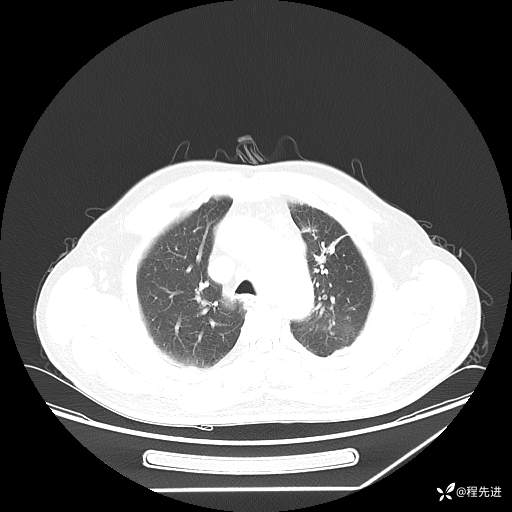

患者性别:男

患者年龄:57岁

简要病史:声嘶2月余

CT平扫+增强: